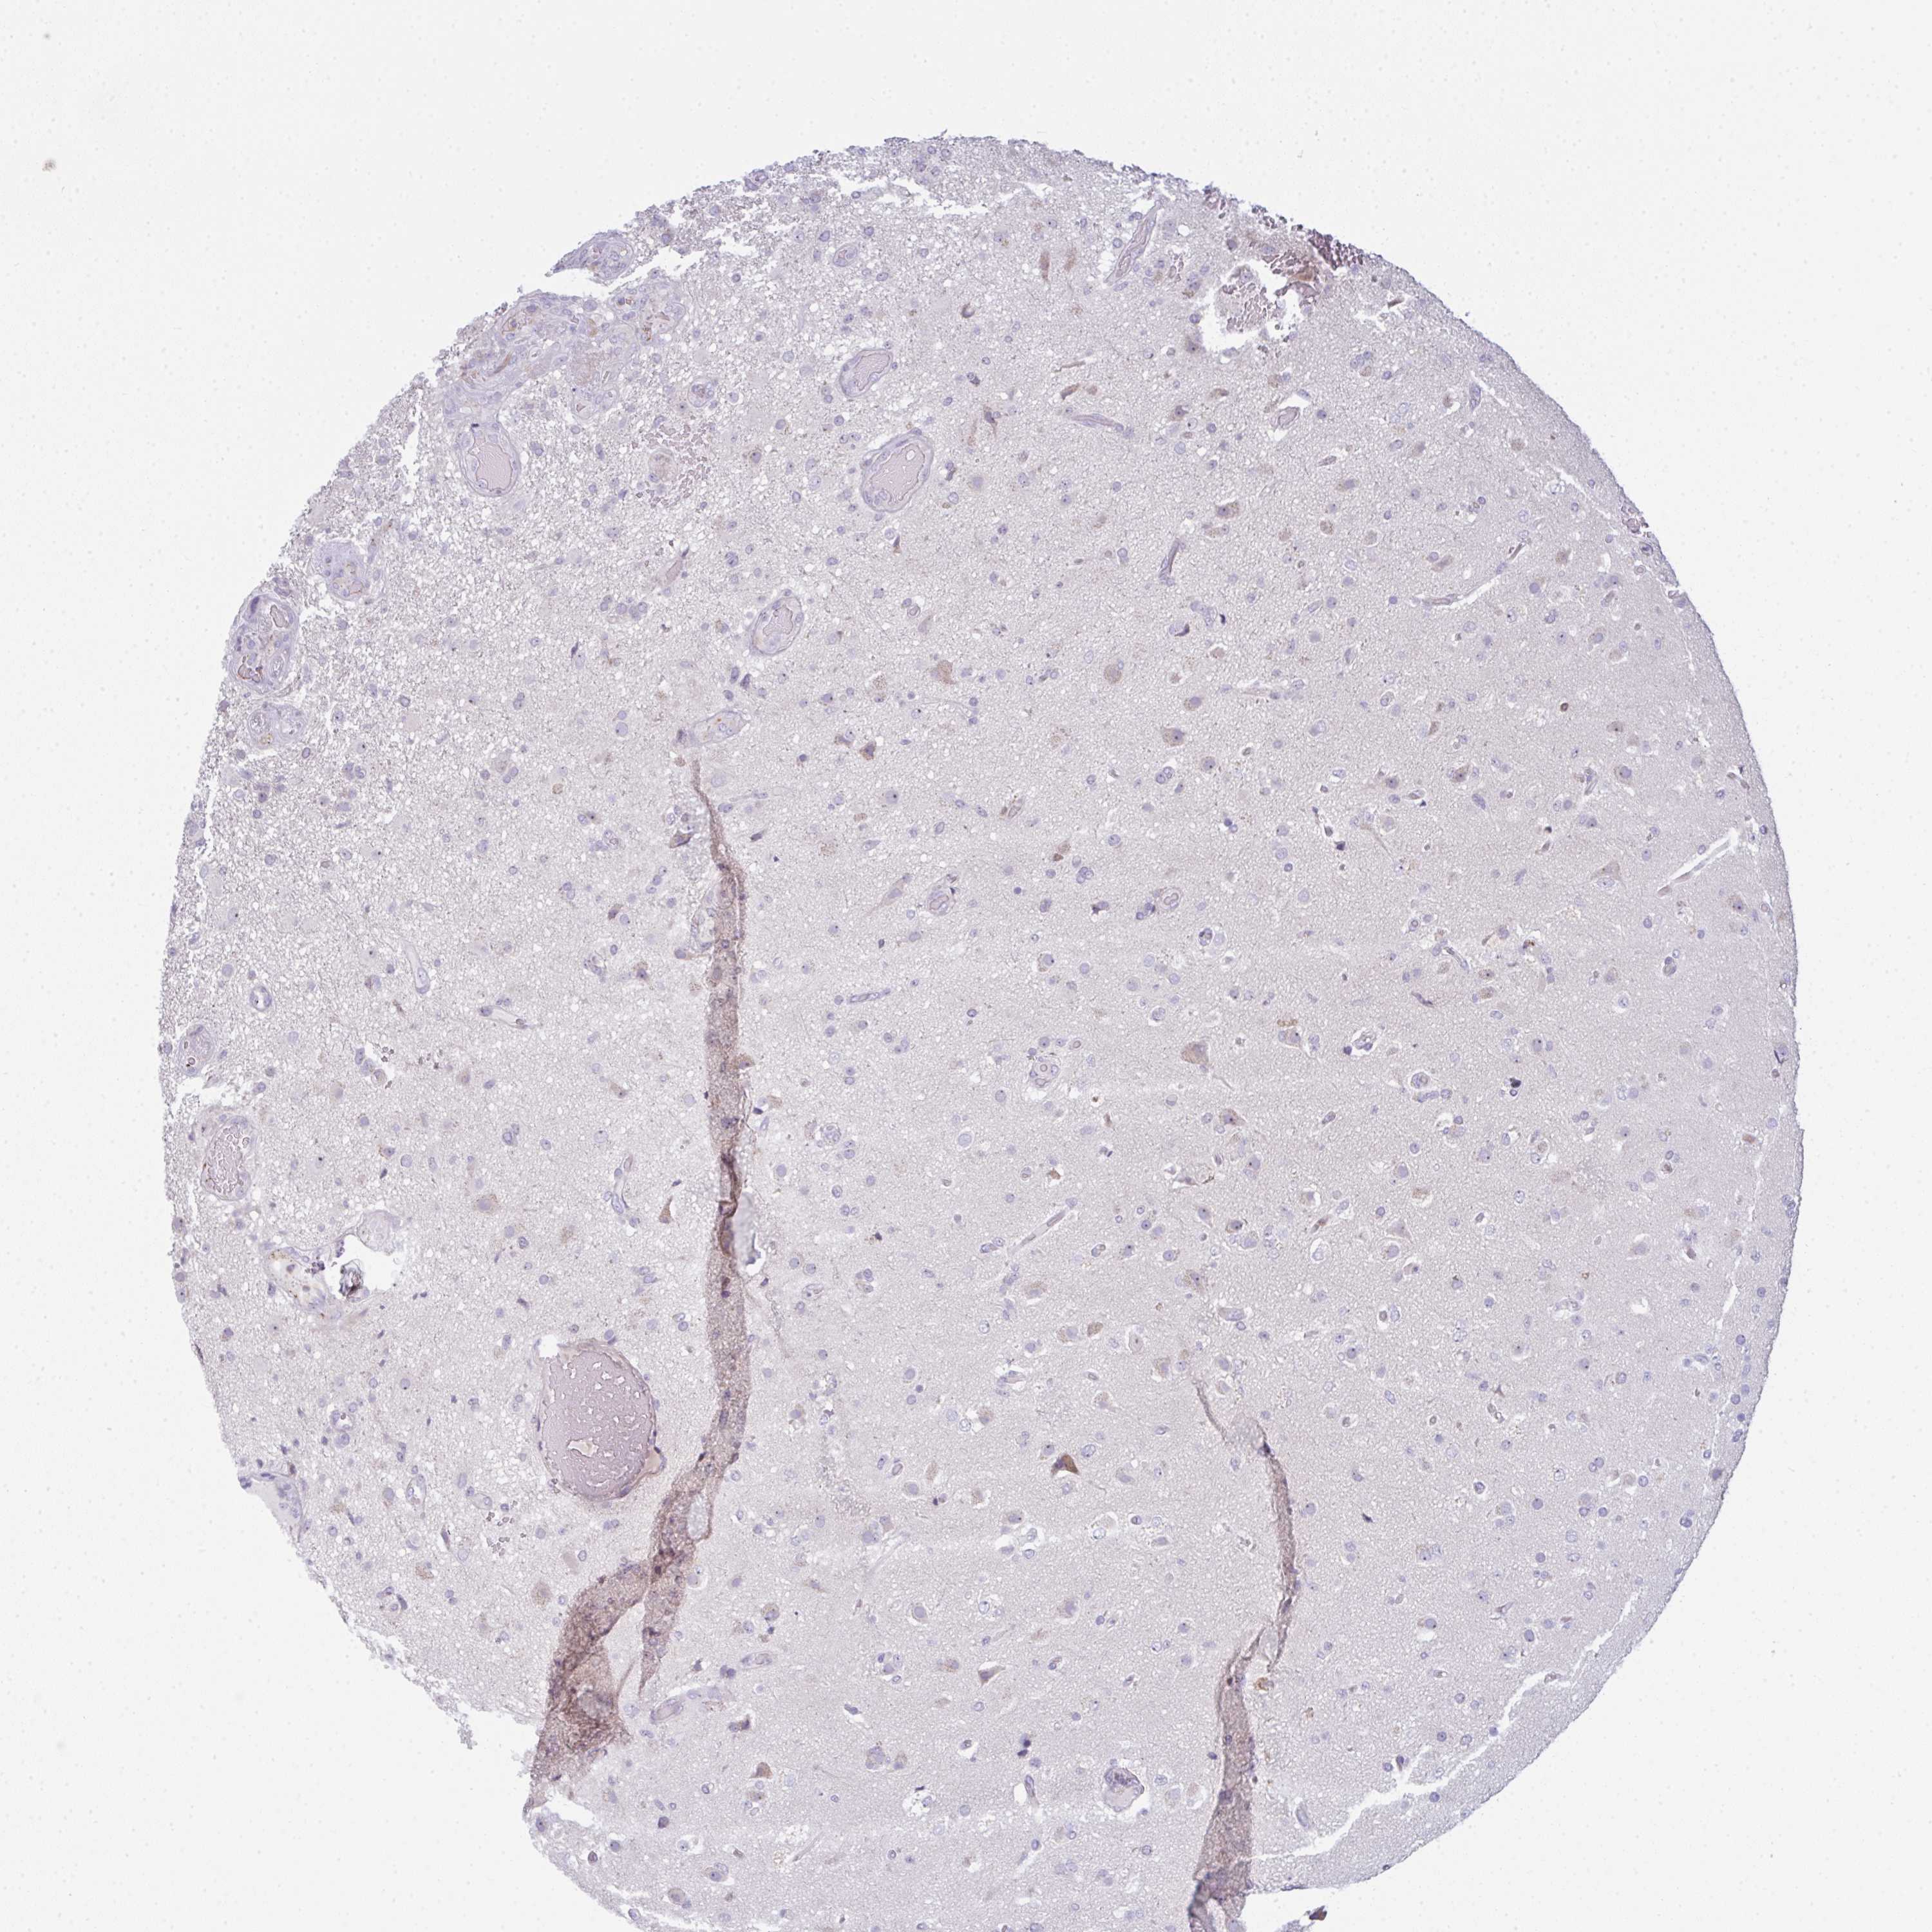

GLIOMA - Protein expressioni

A mouse-over function shows sample information and annotation data. Click on an image to view it in a full screen mode. Samples can be filtered based on level of antibody staining by selecting one or several of the following categories: high, medium, low and not detected. The assay and annotation is described here.

Note that samples used for immunohistochemistry by the Human Protein Atlas do not correspond to samples in the TCGA dataset.

Antibody stainingi

Antibody staining in the annotated cell types in the current human tissue is reported as not detected, low, medium, or high, based on conventional immunohistochemistry profiling in selected tissues. This score is based on the combination of the staining intensity and fraction of stained cells.

Each image is clickable and will lead to virtual microscopy that enables deeper exploration of all samples and also displays staining intensity scores, fraction scores and subcellular localization as well as patient and tissue information for each sample.

Antibody HPA050092

Antibody CAB025368

Glioma, malignant, High grade

Glioma, malignant, Low grade